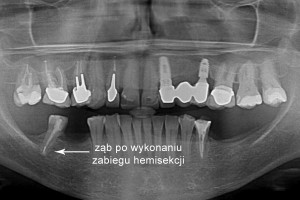

Hemisekcja to zabieg polegający na separacji i usunięciu części korony i korzenia zęba dotkniętego nieodwracalnie procesem patologicznym. Pozwala to na zachowanie fragmentu zęba, który może być wykorzystany jako filar w trakcie dalszej rehabilitacji protetycznej. Pozostały fragment zęba może stanowić filar przy planowanej odbudowie protetycznej.